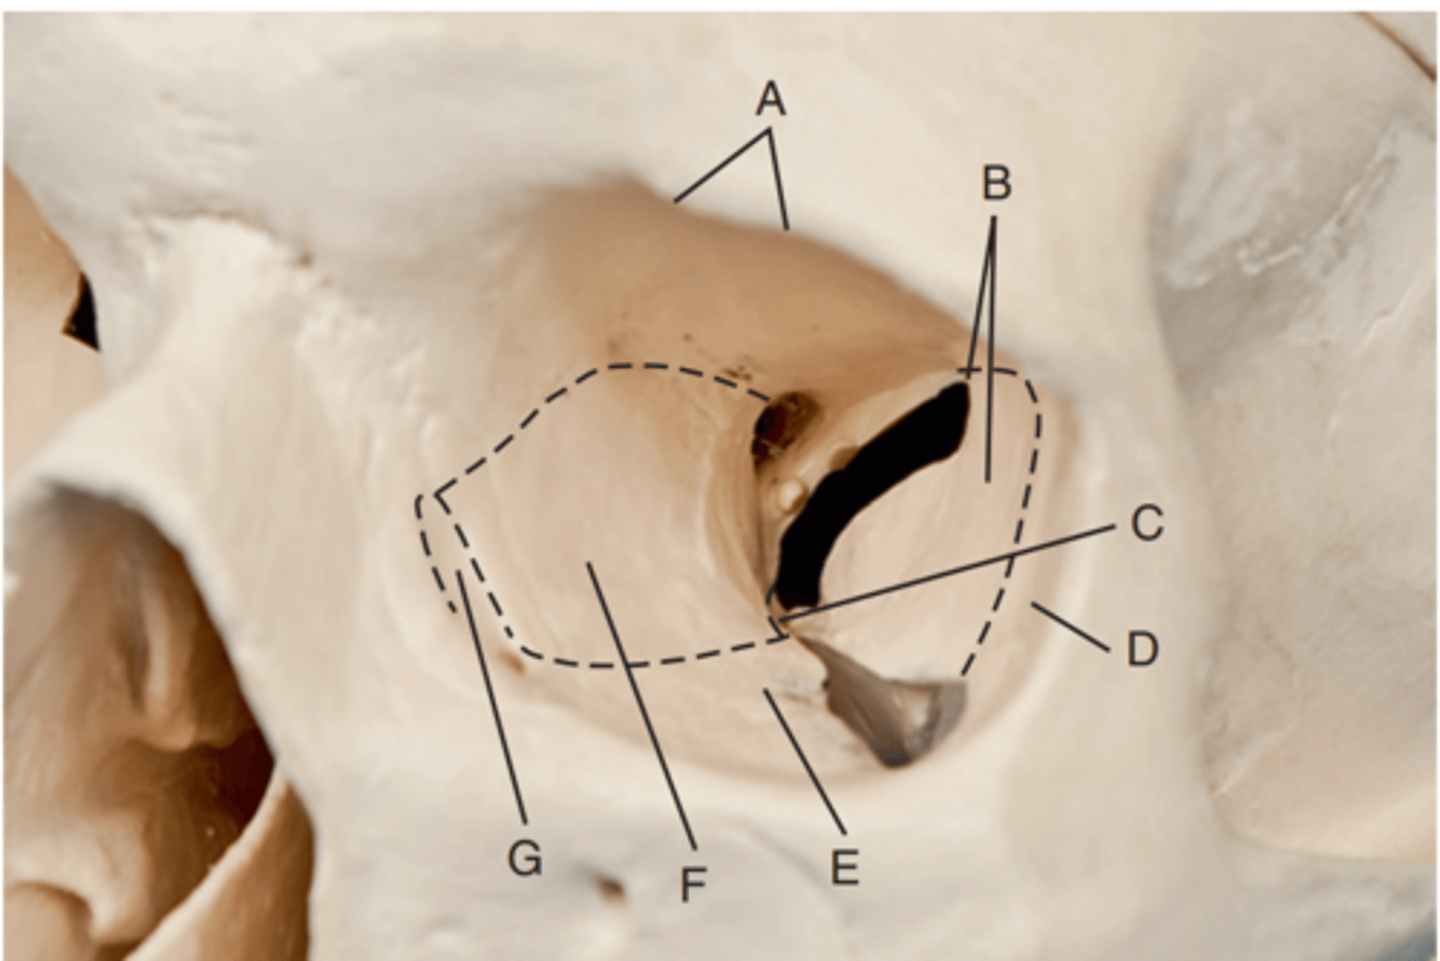

Optic foramen

Label A

Sphenoid strut

Label B

Superior orbital fissure

Label C

Inferior orbital fissure

Label D

Orbital plate of frontal bone

Label A

Sphenoid bone

Label B

Optic foramen and canal

Label C

Superior orbital fissure

Label D

Infraorbital margin (IOM)

Label E

Sphenoid strut

Label F

Lateral orbital margin

Label G

Supraorbital margin

Label H